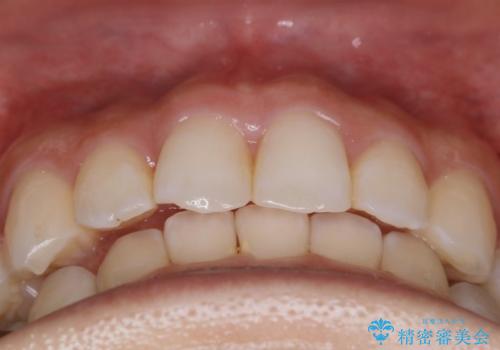

【非抜歯】下の前歯が1本少ない場合の矯正治療

- 前歯のガタつきを主訴に来院されました。

生まれつき下の前歯が1本少なく、その分のスペースを上の前歯がガタつくことで埋めているという状況でした。

上下それぞれのガタつきをとっていく過程で、歯1本分のスペースの差を、上顎の前歯のIPRで調整して並べる方法をご提案させていただきました。